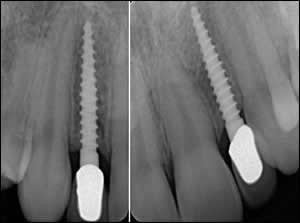

Fig 3: Mini Dental Implants were selected and inserted between the adjacent teeth.

Fig 4: Porcelain fused to metal crowns were inserted to solve this difficult dilemma.